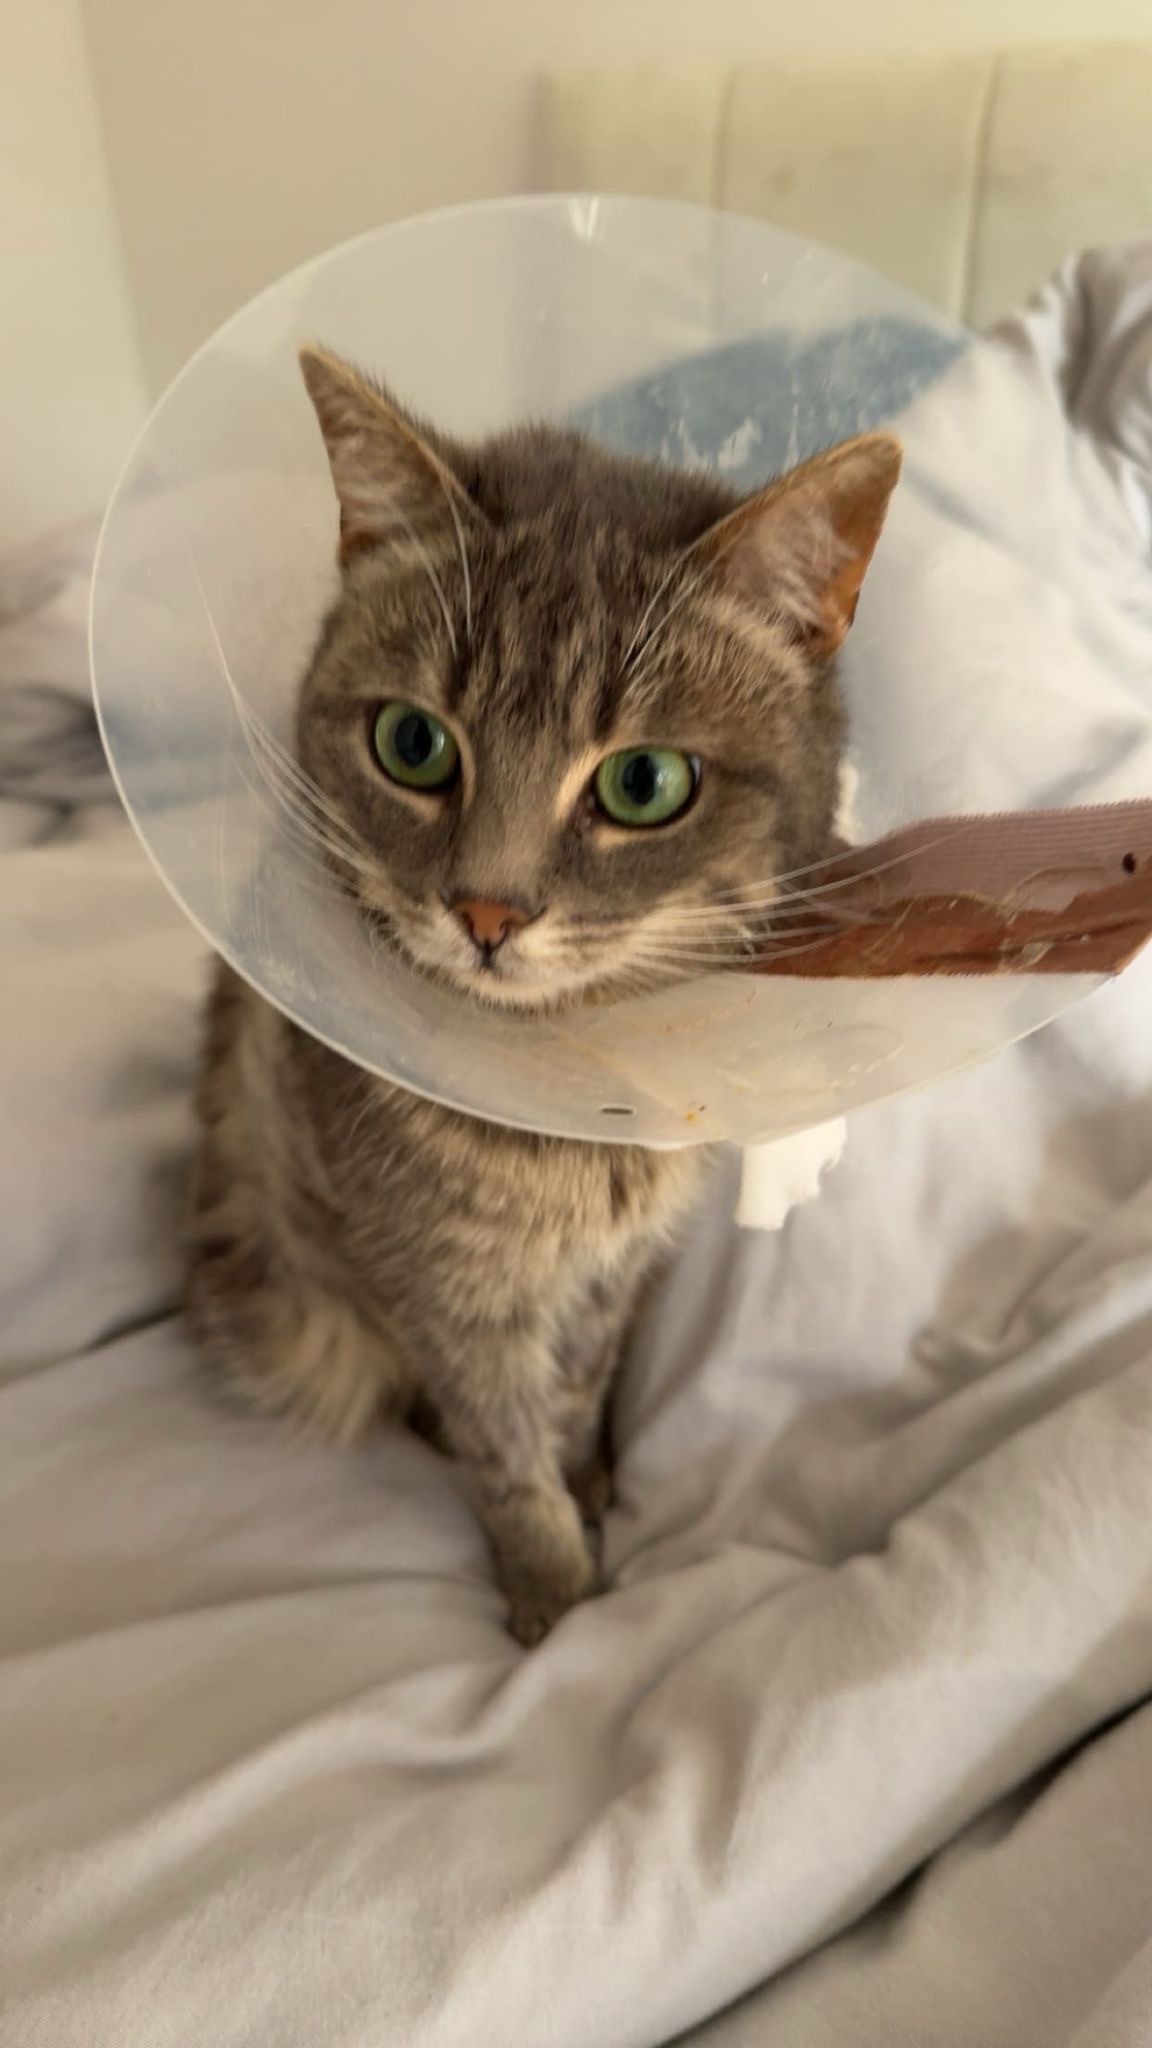

Hallo, das ist eine kurze aber bisher schon sehr harte Geschichte über eine kleine Katze. Emmi ist vor knapp einem Jahr auf einem Bauernhof geboren. Als junges Kätzchen hat sie es geliebt bei den Kühen zu schlafen und hat sich im Stroh versteckt. Als sie dann bei normalen Arbeiten auf dem Hof von einem Traktor Anhänger angefahren wurde musste sie das erste Mal um ihr Leben kämpfen. Doch sie hat es geschafft. Leider konnte sie seit dem Zeitpunkt nicht mehr richtig laufen. Daher hat eine Freundin sie adoptiert. Anfang des Jahres ist dann die Zwillingsschwester von Emmi verstorben. Dann Anfang diesen Monats fing Emmi an zu schwer zu atmen. Anstatt das Besserung eintritt wird es immer schlimmer die Entscheidung steht fest Emmi muss schnellstmöglich in eine Klinik. Die Diagnose: Zwerchfellriss Emmi kämpft bereits das zweite Mal um ihr Leben. Doch wieder einmal schafft sie es sich hoch zu kämpfen. Dann der Schock, die Tierkrankenversicherung übernimmt die Rechnung nicht. 2800€.

Die neue Mutter von Emmi befindet sich jedoch gerade kurz vor dem Examen zur Pflegefachkraft und ist nun finanziell erschöpft.

Wir würden uns freuen wenn wir ihr auf diesem Weg etwas von der finanziellen Last abnehmen können.